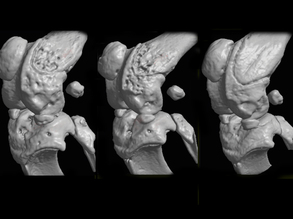

Joints in Jeopardy